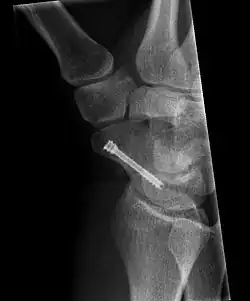

The scaphoid can be slow to heal because of the limited circulation to the bone. Fractures of the scaphoid must be recognized and treated quickly, as prompt treatment by immobilization or surgical fixation increases the likelihood of the bone healing in anatomic alignment, thus avoiding mal-union or non-union.[6] Delays may compromise healing. Failure of the fracture to heal ("non-union") will lead to post-traumatic osteoarthritis of the carpus.[1]: 189 One reason for this is because of the "tenuous" blood supply to the proximal segment.[3] Even rapidly immobilized fractures may require surgical treatment, including use of a headless compression screw such as the Herbert screw to bind the two halves together.

Scaphoid fractures may be difficult to diagnose via plain x-ray. A repeat x-ray may be required at a later date, as might cross-sectional imaging via MRI or CT scan.[6]